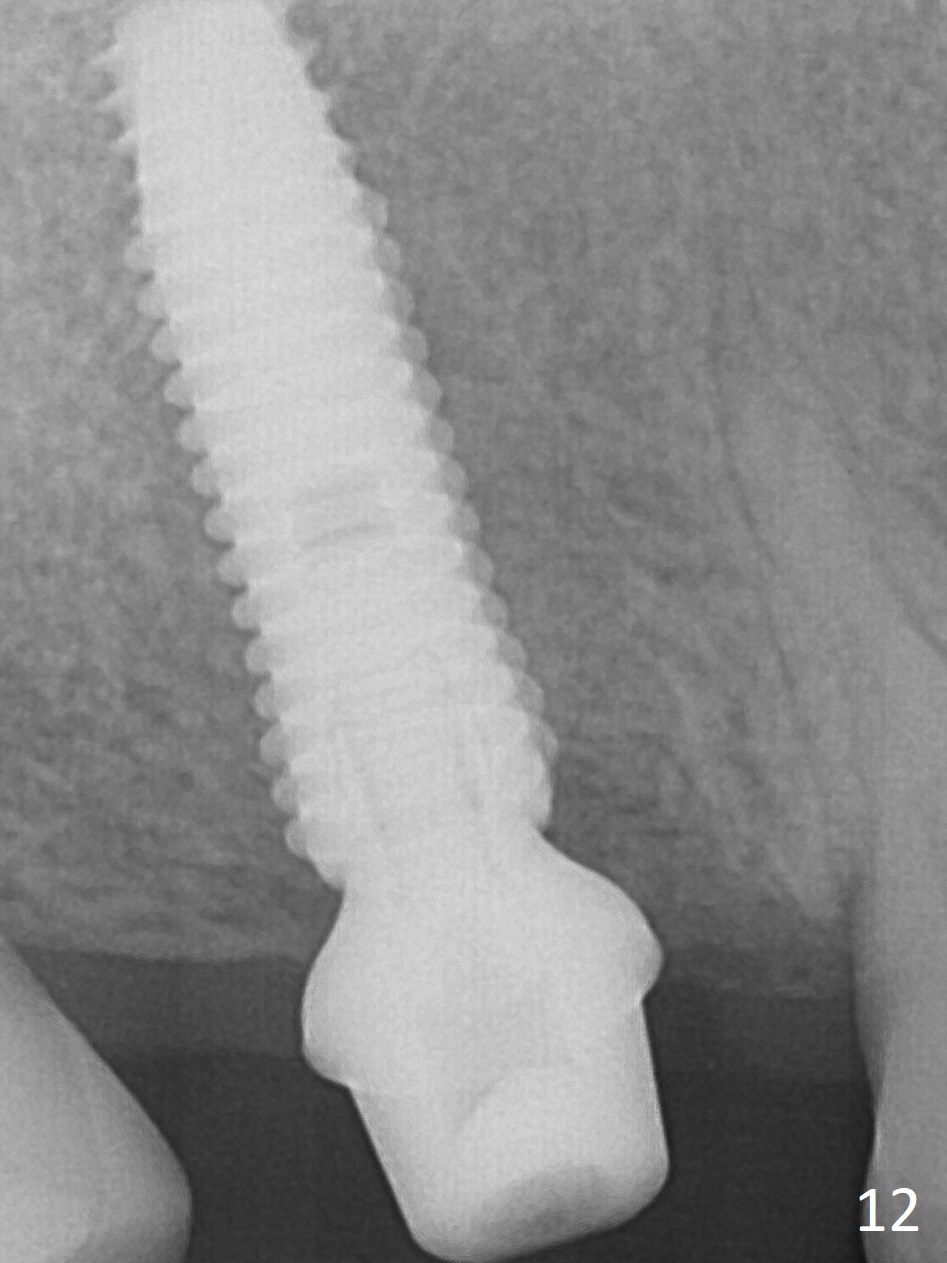

The palatal cusp of the affected 2nd premolar is apparently rotated distal (Fig.1). It is more obvious for the socket (Fig.2): the palatal (P) portion of the socket is more distal than the buccal (B) one. When the gauze is removed (Fig.3), Lindamann bur is used to remove the disto(D)palatal bone of the socket (data not shown), followed by starter drill in the DP wall obliquely (Fig.3'). Once the drill enters the bone for 1-2 mm, the bur is straightened and pushed slightly distal (Fig.3''). Fig.4 shows a parallel pin distal (overcorrect) to the original socket (Fig.4 red dashed line). Sequential osteotomy is conducted until 3.8x13 mm drill for 18 mm (Fig.5): note the 2 steps of the osteotomy (red lines). Since the apical portion of the osteotomy is larger than the drill, a larger implant than expected (5x16 mm) is placed. The implant ends up in the middle of the edentulous area (due to the stepped osteotomy; Fig.6-9; >60 Ncm). Vera allograft is placed (Fig.7-9 *) prior to and after placement of a 6.5x4(3) mm abutment (Fig.8-10). The remaining socket opening is sealed with a piece of Collagen plug (Fig.10 *). The socket is then closed by an immediate provisional (Fig.11 P). The abutment is retightened 2 months postop (Fig.12,13). The crown is cemented 4.5 months postop. Panoramic X-ray and CT are taken nearly 7 months post cementation (Fig.14,15) when the patient is ready for #30 implant guide preparation.